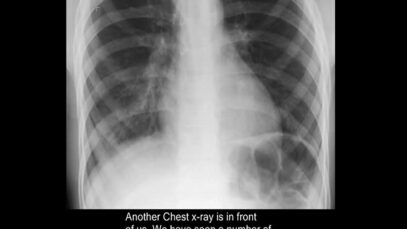

computed tomography of the chest Computed tomography (CT) is an imaging technique that has revolutionized medical imaging. It is widely available, fast, and provides a detailed view of the internal organs and structures. Helical CT is most common, but conventional, axial, step-and-shoot CT is used for thin section high-resolution CT scanning of the lungs, coronary […]